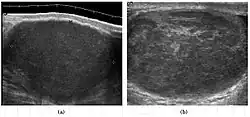

![]() Sonography of a normal testis. The normal testis presents as a structure having homogeneous, medium level, granular echotexture. The mediastinum testis appears as the

hyperechoic region located at the periphery of the testis as seen in this figure. | |

The normal adult testis is an ovoid structure measuring 3 cm in anterior-posterior dimension, 2–4 cm in width, and 3–5 cm in length. The weight of each testis normally ranges from 12.5 to 19 g. Both the sizes and weights of the testes normally decrease with age. At ultrasound, the normal testis has a homogeneous, medium-level, granular echotexture. The testicle is surrounded by a dense white fibrous capsule, the tunica albuginea, which is often not visualized in the absence of intrascrotal fluid. However, the tunica is often seen as an echogenic structure where it invaginates into the testis to form the mediastinum testis. In the testis, the seminiferous tubules converge to form the rete testes, which is located in the mediastinum testis. The rete testis connects to the epididymal head via the efferent ductules. The epididymis is located posterolateral to the testis and measures 6–7 cm in length. At sonography, the epididymis is normally iso- or slightly hyperechoic to the normal testis and its echo texture may be coarser. The head is the largest and most easily identified portion of the epididymis. It is located superolateral to the upper pole of the testicle and is often seen on paramedian views of the testis. The normal epididymal body and tail are smaller and more variable in position.